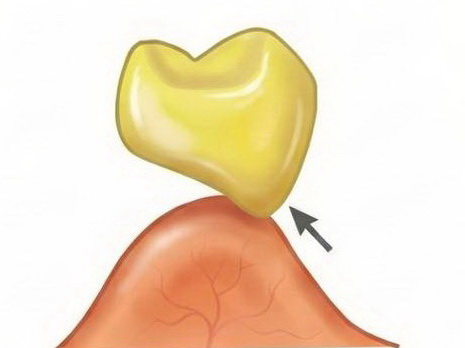

Răng giả nhịp cầu dạng ôm sống hàm cải biên (Modified Ridge Lap Pontic)

- Tiếp xúc: Là dạng cải tiến của kiểu ôm sống hàm, trong đó răng giả chỉ tiếp xúc sống hàm ở mặt ngoài và ngay đỉnh sống hàm. Mặt trong được thiết kế lồi và không chạm niêm mạc.

- Đặc điểm: Diện tiếp xúc mô giảm đáng kể so với dạng yên ngựa hoặc ôm sống hàm cổ điển.

- Thực tế trong lâm sàng: Tính thẩm mỹ mặt ngoài tốt nhưng nhưng vẫn khó vệ sinh mặt trong, bệnh nhân thường khó chịu khi bị đọng thức ăn vùng mặt trong.